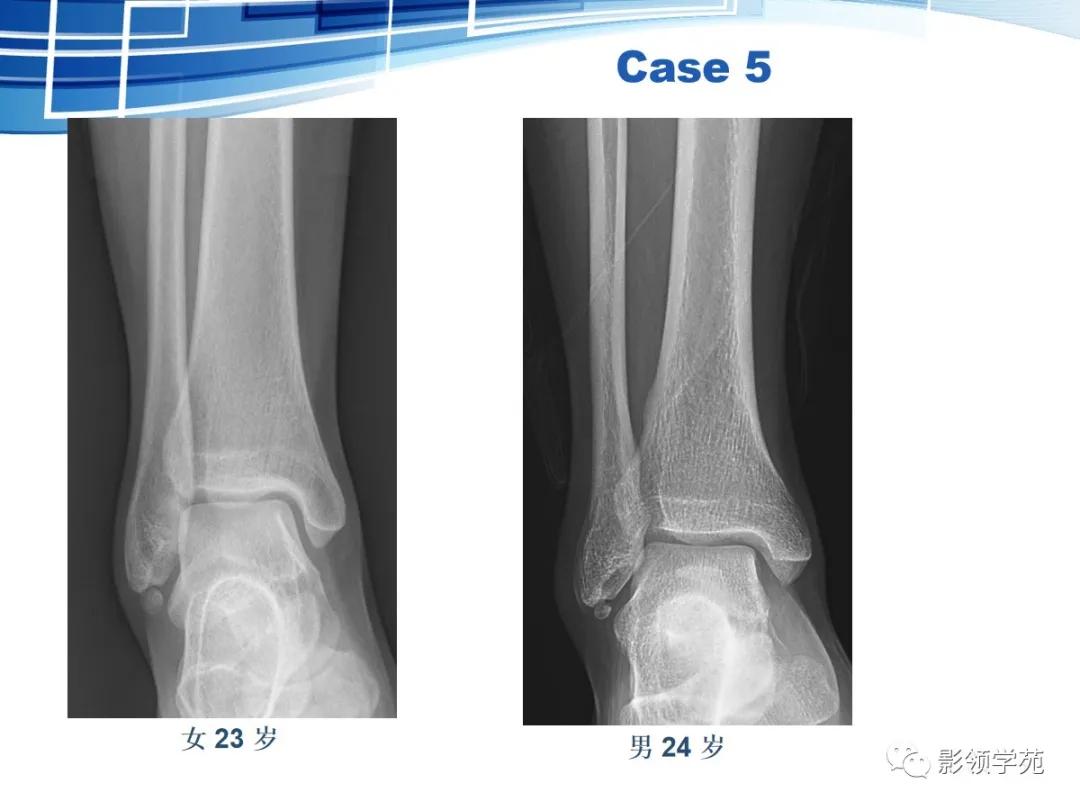

虽然撕脱性骨折与永存骨骺、籽骨和副骨在影像学上均有游离的小骨块影的表现,但前者具有骨折的影像学一般特征,而后三者不具有。

永存骨骺、籽骨和副骨的发生与其特有部位及典型特征紧密联系。

常见案例均具有骨块边缘钝圆、骨皮质连续、局部软组织无明显肿胀以及伤后该骨的连续摄片无明显变化等非撕脱性骨折的共同特点。

鉴别重点:独立的骨结构(游离骨)若与相对骨的缺损缘相吻合,是撕脱,如有外伤,更支持。

籽骨、副骨与永存骨骺一般边缘光滑, 周围皮质密度较高, 皮质光整, 附近骨质结构完整, 具有对称性, X线随诊形态及位置不会发生改变, 一般不会引起疼痛。但个别患者由于一些局部肌肉的扭伤而引起副骨的移位, 或由于机械外力的作用使副骨摩擦软组织导致滑囊炎和肌腱炎, 甚至由于长期慢性磨损可与附近正常骨质形成假关节从而产生创伤性关节炎可引起疼痛。而骨折一般具有明确的外伤史, 附近软组织肿胀明显, 疼痛症状明显, 断端锐利, 皮质断裂, 不具有对称性, X 线随诊形态及位置可发生移位。而籽骨、副骨与永存骨骺本身也可在外伤的情况下发生骨折, 但极罕见。